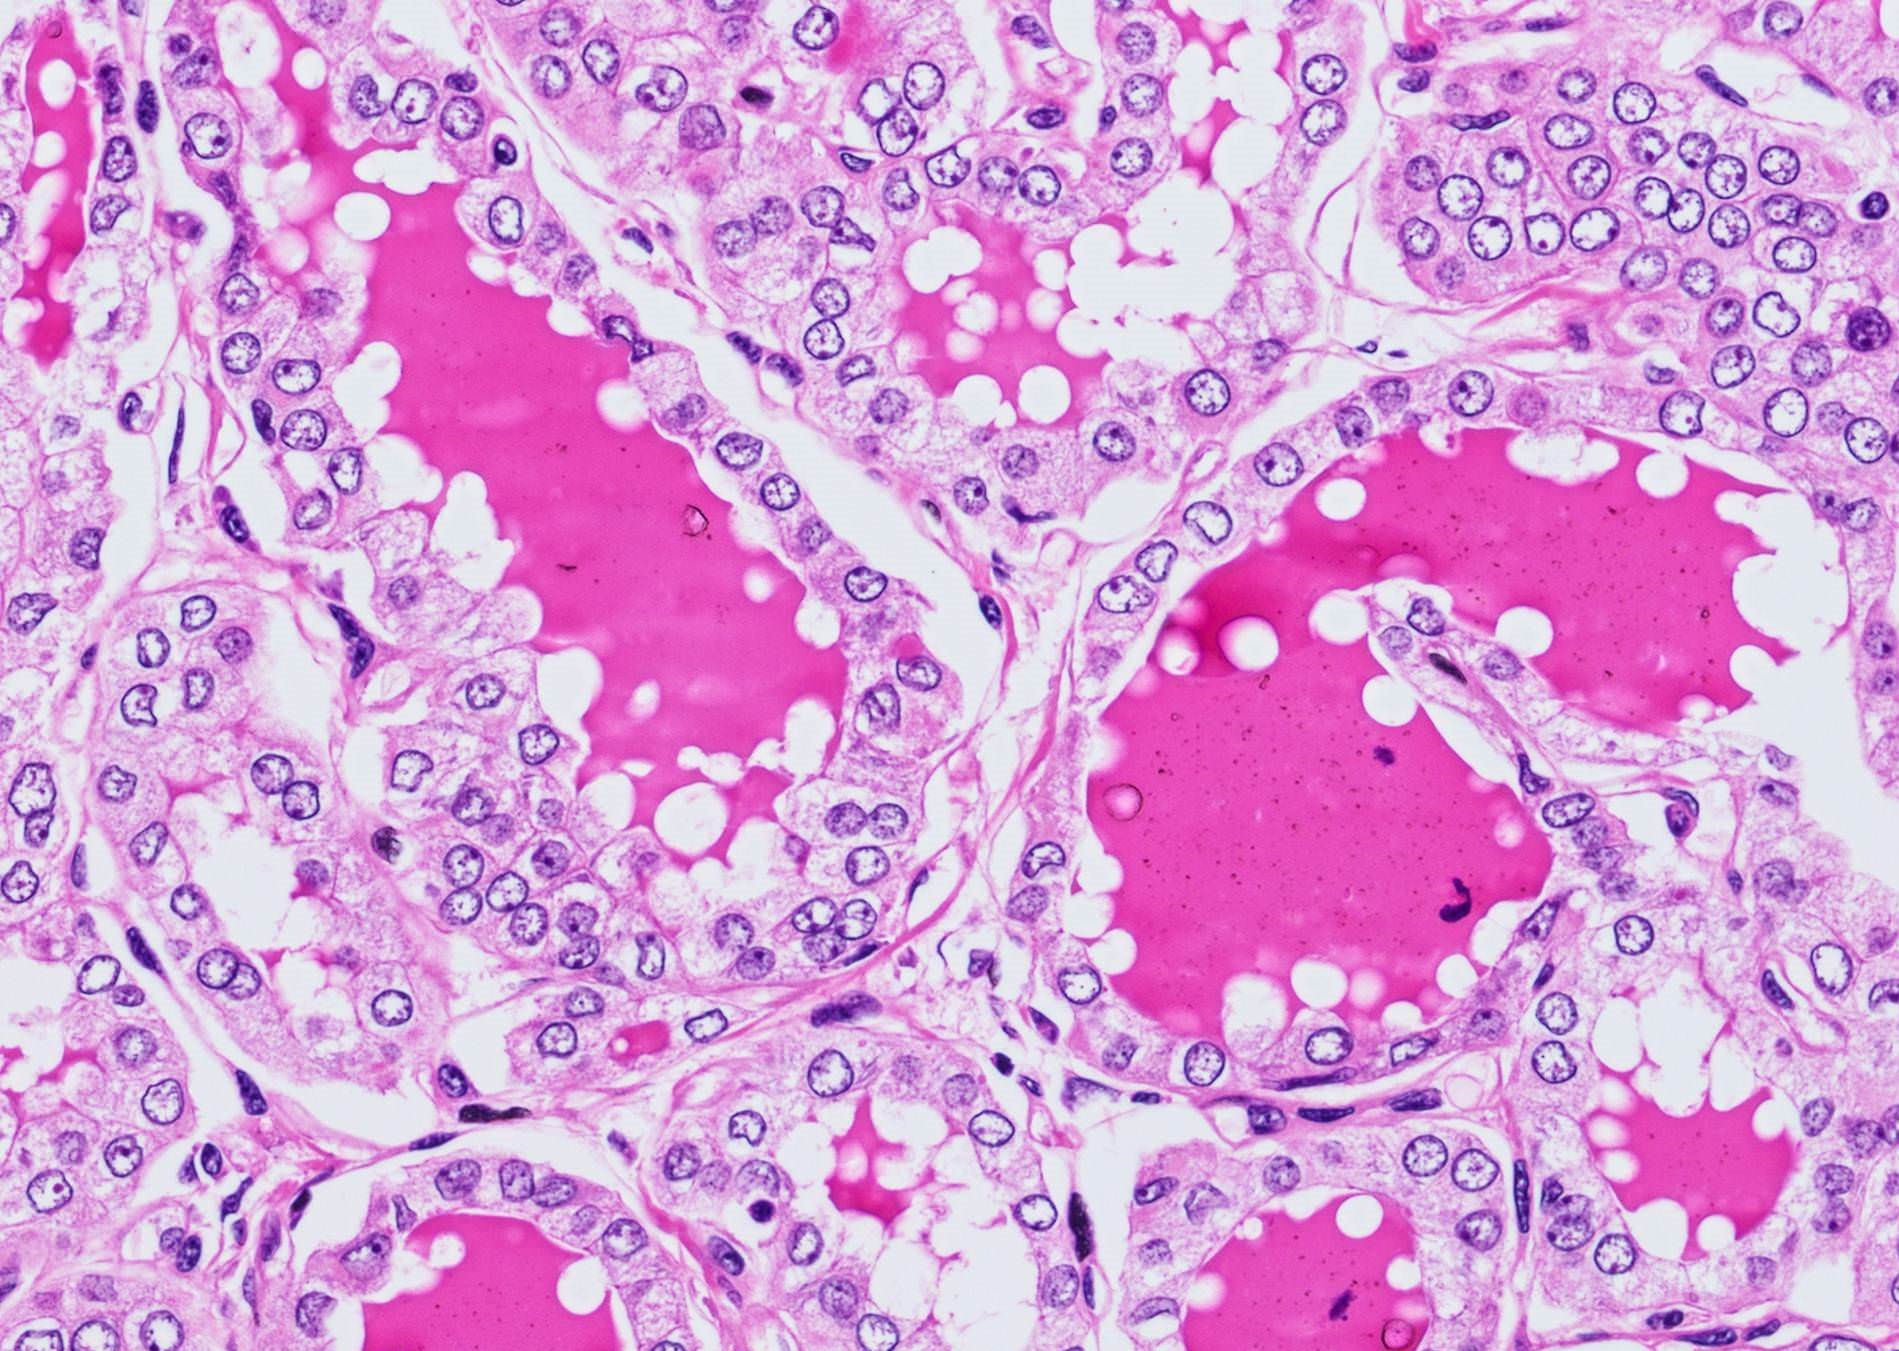

Microscopic (histologic) description

- Nuclear features of papillary thyroid carcinoma should be seen multifocally (at least 2 foci) or diffusely within the tumor; such features include nuclear enlargement, nuclear overlapping, chromatin clearing, nuclear membrane irregularity and nuclear grooves (J Clin Endocrinol Metab 2017;102:15)

- Architecture: exclusively or nearly exclusively follicular

- True papillae with fibrovascular core are in general absent in follicular variant

- "Bubble gum colloid", i.e. dense homogenous hypereosinophilic colloid, may be seen in the lumen of neoplastic follicles; scalloping of colloid may be seen

Microscopic (histologic) images